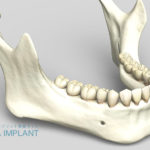

名前のとおり外科手術を2回行います。1回目の手術でインプラントを顎の骨に埋め込み、一度歯茎を閉じてインプラントと骨が結合する(3から6ケ月)のを待ちます。1回法の手術より期間は長くかかってしまいますがインプラントと骨を癒着する期間が長く、感染症の発症リスクが低いのが特徴です。

通院期間…3~7ヶ月